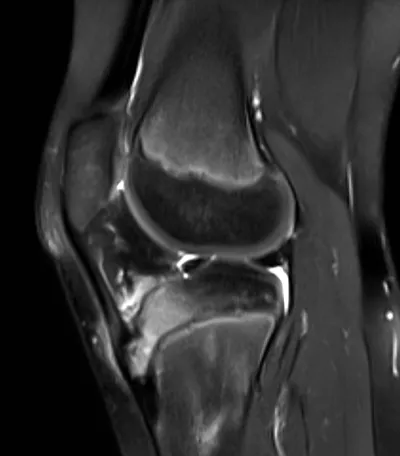

Apophysitis Radiology Images

Browse 3 medical images tagged with apophysitis. This collection includes various imaging modalities for medical education and reference.

About Apophysitis Imaging

- This collection contains 3 radiology images related to apophysitis, including various imaging modalities such as X-rays, MRIs, CT scans, and ultrasound images commonly used in medical diagnosis and education.